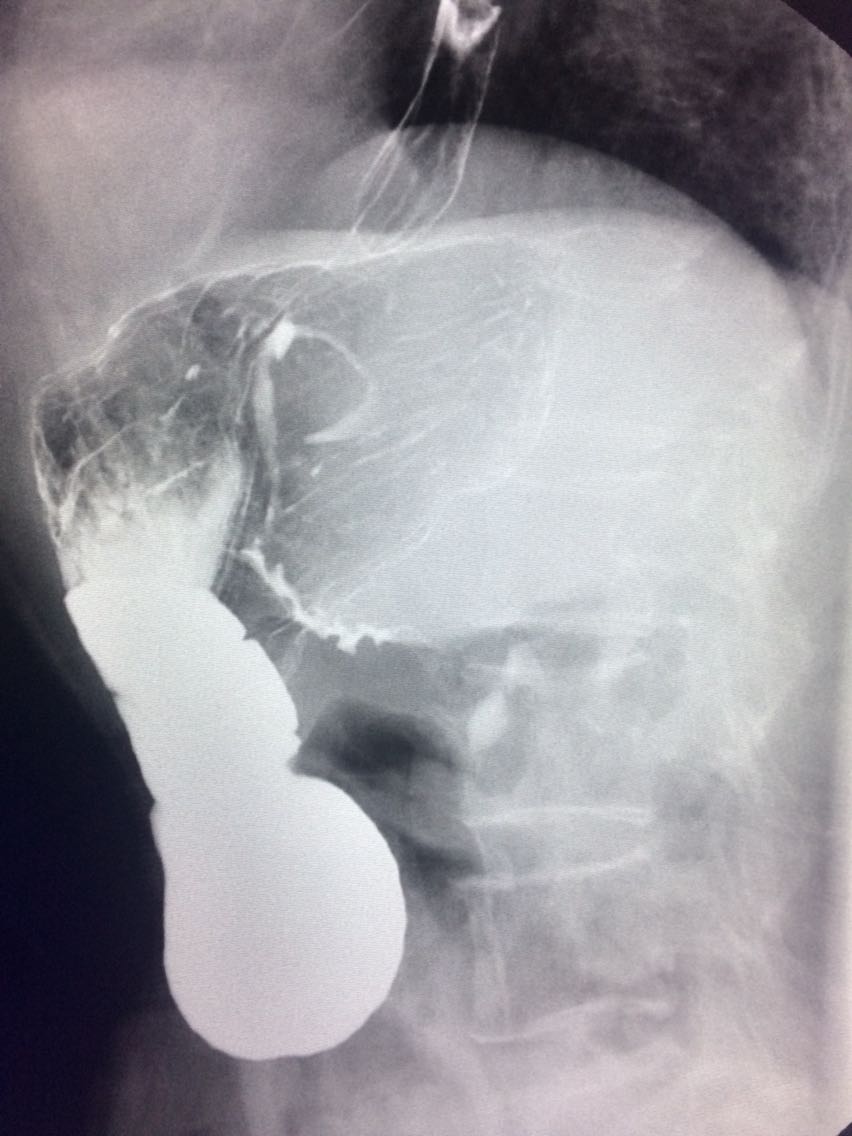

查体未见明显异常。 上消化道造影如图。

诊断食管癌。 造影剂逆流入胆道。